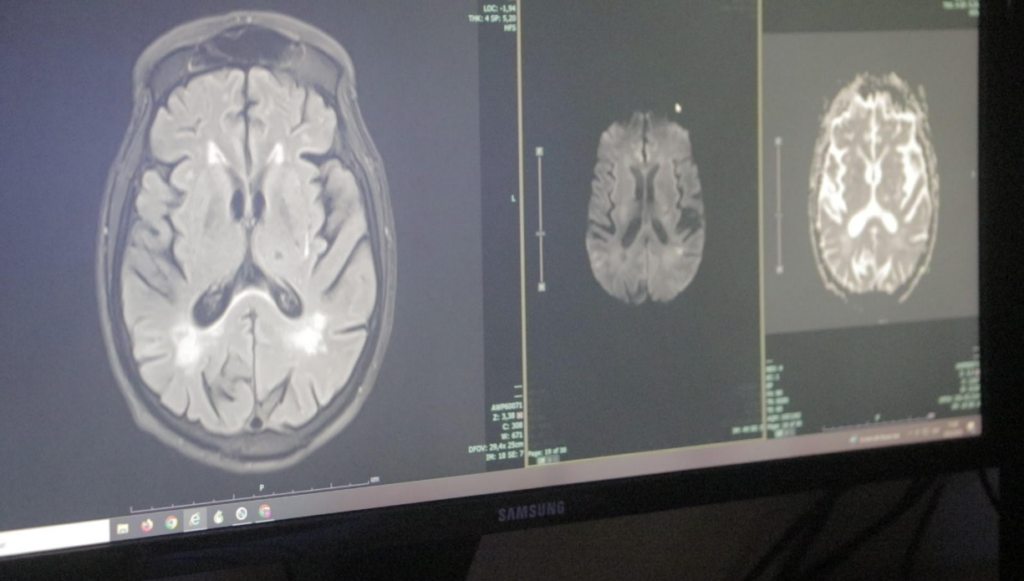

“No toda persona que convulsiona tiene epilepsia” y que las herramientas diagnósticas modernas como el electroencefalograma, estudios de imágenes y análisis clínicos permiten ofrecer tratamientos más precisos.

El enfoque no se limita solo al tratamiento con medicamentos anticonvulsivos, sino que también integra opciones avanzadas para quienes no responden a fármacos, como la cirugía de epilepsia, dietas terapéuticas (como la cetogénica) y dispositivos de neuromodulación como el estimulador del nervio vago ya implementado en varios pacientes con buenos resultados.